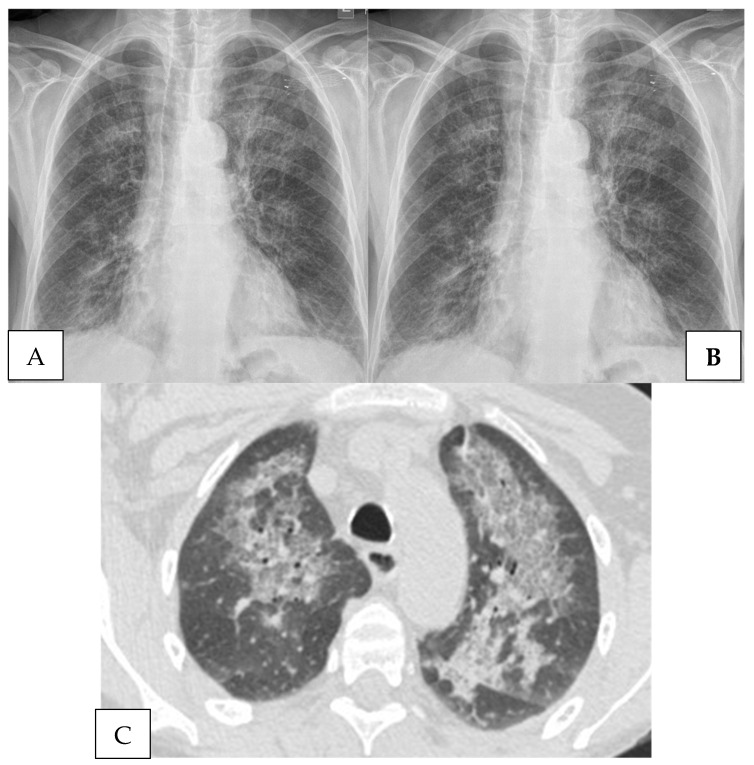

Pneumocystis jiroveci remains an important fungal pathogen in immunocompromised hosts. The environmental reservoir remains unknown. Pneumonia (PJP) results from airborne transmission, including in nosocomial clusters, or with reactivation after an inadequately treated infection. Pneumocystis pneumonia most often occurs within 6 months of organ transplantation, with intensified or prolonged immunosuppression, notably with corticosteroids and following cytomegalovirus (CMV) infections. Infection may be recognized during recovery from neutropenia and lymphopenia. Invasive procedures may be required for early diagnosis and therapy. Despite being a well-established entity, aspects of the pathogenesis of PJP remain poorly understood. The goal of this review is to summarize the data on the pathogenesis of PJP, review the strengths and weaknesses of the pertinent diagnostic modalities, and discuss areas for future research.